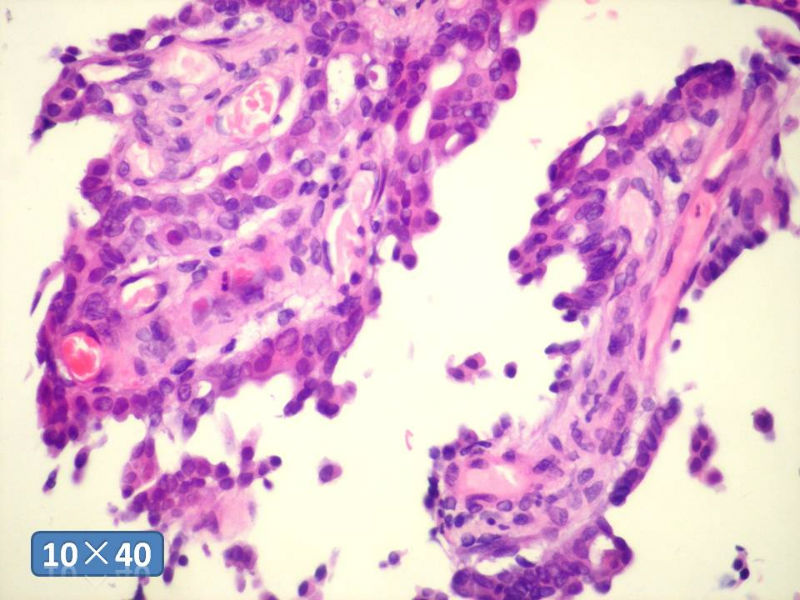

只能说是乳头状瘤

是不是导管内

乳头状瘤 and 导管内乳头状瘤 are the same; Benign lesion.

After you work up and you still cannot be sure it is benign , atypical or maignant lesion, you can call 乳头状lesion.

If this is excisonal case, you should figure out the nature of the papillary lesion.

我的意思就是提醒大家 在不是很确定的情况下 尽量少给自己套枷锁